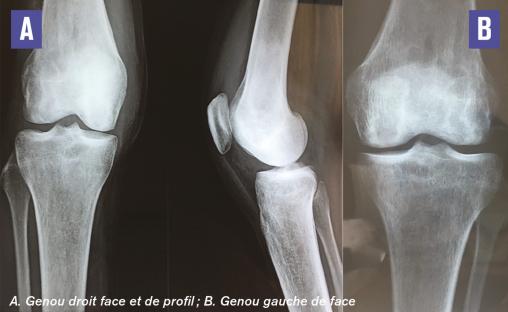

Cette femme de 24 ans consultait pour des gonalgies bilatérales mécaniques évoluant depuis 3 mois. La patiente était maigre (IMC à 14), sa marche était précautionneuse, sans trouble neurologique. L’interrogatoire notait un tabagisme chronique depuis l’âge de 18 ans et une corticothérapie en automédication à raison de 40 mg/j pendant 18 mois. La fonction articulaire était bonne, douloureuse à la mobilisation des genoux. Il n’y avait pas d’épanchement articulaire ni de signes en relation avec une maladie de système ou de surcharge. La radiographie notait quelques plages d’ostéocondensation inhomogènes des condyles fémoral et tibial droits, et une déminéralisation osseuse hétérogène des deux condyles fémoraux et du plateau tibial gauche (fig. 1 ). L’IRM montrait des images d’os dans l’os caractéristiques d’infarctus osseux (fig. 2 ). Le bilan biologique et l’échographie abdominale étaient normaux. Les autres causes ayant été exclues en raison de la normalité des explorations, les infarctus osseux étaient liés à la corticothérapie au long cours.